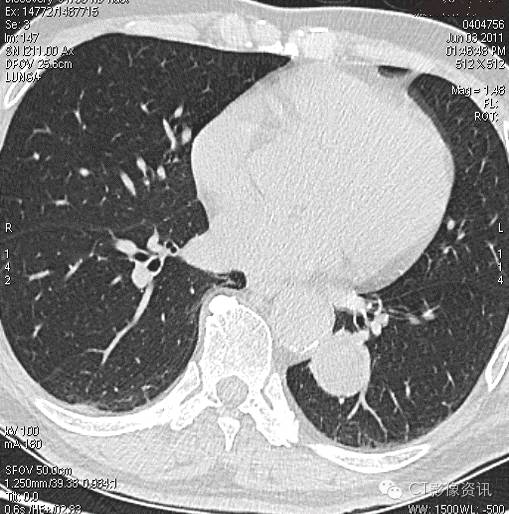

扫描和分析方法 以下病例采用宝石CT能谱成像模式(GSI)扫描,获得增强的能谱图像。通过分析不同肺结节静脉期能谱曲线形态,结合定量指标,对照病理结果,回顾性总结肺部结节能谱成像的临床意义以及能谱曲线在肺结节中鉴别要点。

肺结节的能谱CT鉴别诊断要点 能谱衰减曲线:以静脉期明显; 在低KeV区差异明显; 速降型——恶性、炎性,缓降型——结核、良性,平台型(反向)——囊变坏死区、脂肪; 肺癌和炎性病变中央区的NIC值具有显著的差异,因此NIC值对鉴别肺结节良、恶性病变具有高敏感性与特异性; 肺癌和炎性病变的能谱衰减曲线斜率(λHU)具有显著的差异。

结论 结合NIC值与λHU值,能谱曲线可以对肺结节病变进行有效的鉴别诊断。